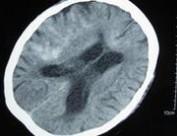

老年人蛛網膜下腔出血

• 老年人蛛網膜下腔出血

628健康網為您分享有關老年人蛛網膜下腔出血的癥狀,老年人蛛網膜下腔出血的治療方法,老年人蛛網膜下腔出血的預防知識...